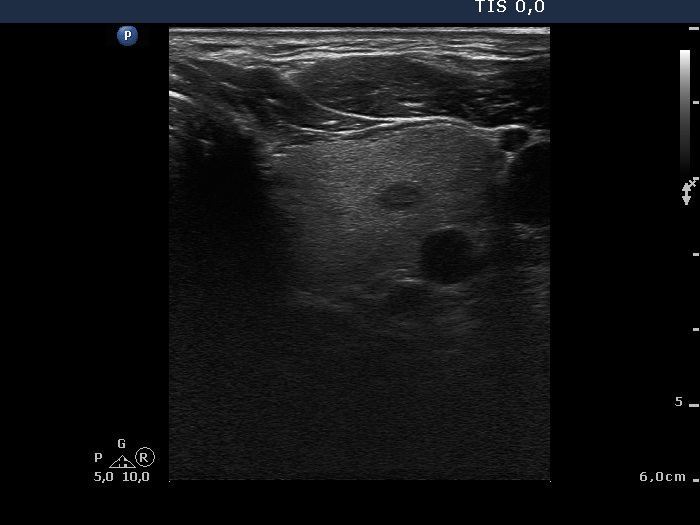

Ultrasonography: The thyroid was echonormal with a few insignificant lesions. There was a large cystic lesion dorsal to the lower third of the right lobe.

After aspiration of 10 ml yellow fluid the size of the lesion decreased from 35x31x42 mm to 29x22x39 mm. The patient refused to aspirate more fluid because her complaints ended.